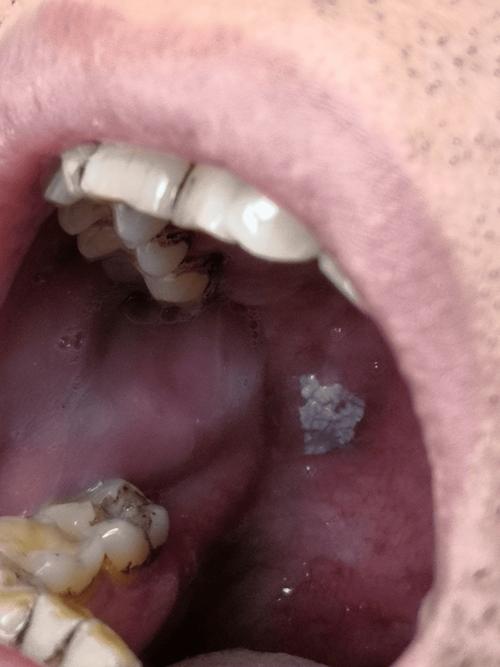

红斑或白斑(“变色”)

这是口腔粘膜的癌前病变,需要高度警惕。

- 红斑: 表现为鲜红色天鹅绒样的斑块,边界清晰,表面光滑或轻微凹陷,触摸时质地较硬,没有明显疼痛感,但易出血。

- 白斑: 是最常见的癌前病变,表现为口腔粘膜上的白色斑块,不能被擦掉,如果白斑表面变得粗糙、增厚、硬结、出现裂纹或溃疡,癌变风险会急剧升高。

- 颗粒状白斑: 尤其是在口底和舌腹部的白色颗粒状区域,癌变风险很高。

- 注意: 并非所有白斑都会癌变,但出现上述变化时,必须立即就医。